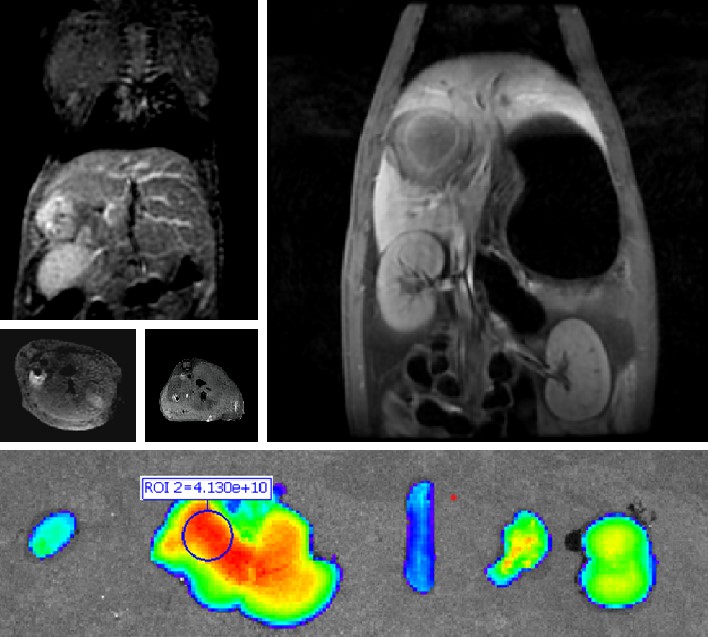

640 (8).jpg

普利制药自主研发双模态造影剂PL002,首次提出通过整合磁共振技术,弥补现有荧光染料假阳性率高、透射深度有限等的短板,进而提升手术的精确性,降低手术过程中的风险,是全球首个获批临床试验的荧光/磁共振双模态造影剂,目前也已经获得美国FDA临床试验批件

640 (9).jpg